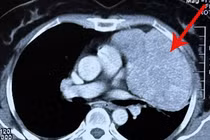

U trung thất là khối u nằm ở trong lồng ngực, phát triển lặng lẽ và ít khi được phát hiện sớm. Nếu không được phát hiện, phẫu thuật loại bỏ kịp thời có thể chèn ép vào tim, phổi, mạch máu lớn….

(khoahocdoisong.vn) - U trung thất bắt nguồn từ những mô của nhiều lá thai, nằm lạc chỗ, phát triển chậm. Khi khối u khá to sẽ gây hiện tượng chèn ép hoặc thoái hóa ác tính.

(khoahocdoisong.vn) - U không chỉ chèn ép vào phổi, tim mà cả các dây thần kinh gây nhiều tai biến nguy hiểm cho tính mạng người bệnh. Phẫu thuật điều trị rất khó khăn.

U trung thất trước chiếm tỷ lệ cao nhất, bao gồm u tuyến hung, u tế bào mầm… 30 – 50% các trường hợp u trung thất không có biểu hiện hoặc có một số biểu hiện không đặc trưng như: Đau ngực, khó thở, ho, sốt… Khối u vùng trung thất thường gây ra hội chứng chèn ép tĩnh mạch chủ, tim, phổi, nên rất nguy hiểm cho bệnh nhân bất cứ lúc nào. Với kỹ thuật mổ nội soi tại Bệnh viện Phổi T.Ư đã mang lại thành công và may mắn cho nhiều bệnh nhân.